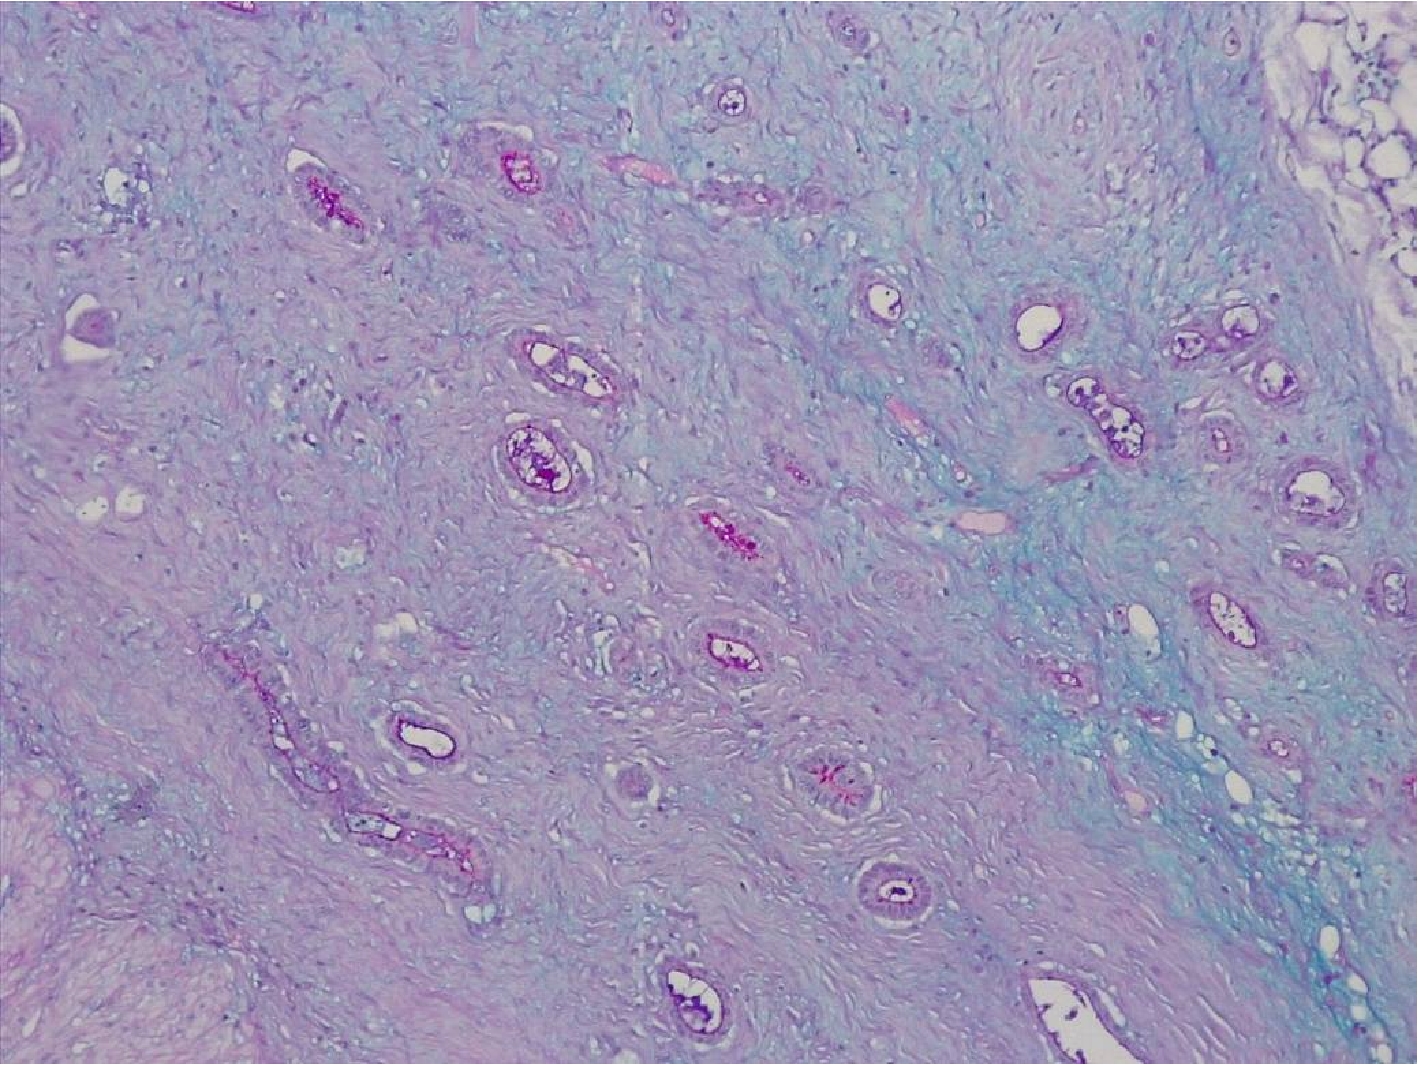

Строма вокруг опухоли была представлена рыхлой волокнистой соединительной тканью с признаками миксоматоза, с немногочисленными тонкими коллагеновыми волокнами, с экспрессией виментина (рис.3).

Рис.3. Строма аденокарциномы тонкой кишки с нейроэндокринным компонентом представлена немногочисленными тонкими коллагеновыми волокнами. Иммуногистохимическое исследование с антителами к виментину. Увеличение Х200.